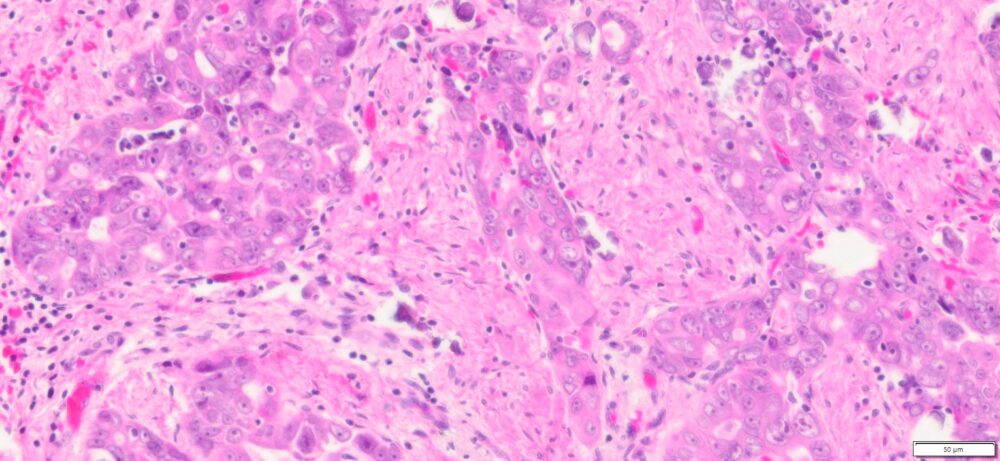

Description

| Organ& Tissue | Pathology Diagnosis | Gender/Age | % Tumor Area | Grade | TMN Stage | IHC Biomarkers |

| Human Ovary | High Grade Serous Carcinoma (HGSC) FFPE Sections | Female/61 | 30% | III | pT3cpNxMx | NA |

More Images of H&E Stain and IHC